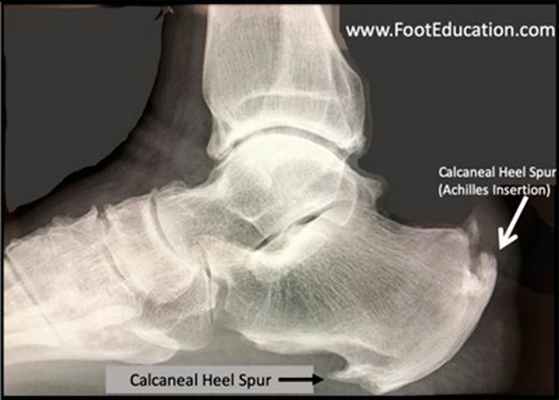

Пяточная шпора представляет собой остеофит пяточной кости. Этиологией шпор является наследственность, нарушения обмена веществ, туберкулез, ревматоидный артрит и системные воспалительные заболевания. К буграм пяточной кости прикрепляется множество мышц и подошвенная фасция, которые оказывают тракционное усилие на кость. Если пяточная шпора располагается на задней поверхности пяточной кости, то это дорсальная пяточная шпора, если она находится по подошвенной поверхности, то это подошвенная пяточная шпора. Дорсальные шпоры часто ассоциируются с тендинопатией ахиллова сухожилия, в то время как подошвенная шпора связана с подошвенным фасциитом. Вершина шпоры находится либо в месте прикрепления фасции на медиальном бугорке пяточной кости, либо в месте прикрепления мышцы короткого сгибателя пальца. Подошвенная фасция во время ходьбы претерпевает постоянное растяжение в связи с ритмичным опусканием и подъемом свода стопы, что приводит к хроническому растяжению апоневроза, которое предрасполагает к воспалительной реакции. Пронация стопы вызывает асимметричное натяжение подошвенной фасции. Избыточная пронация приводит к увеличению натяжения подошвенного апоневроза в месте прикрепления к бугру пяточной кости и считается основным механическим фактором развития подошвенной пяточной шпоры. Хроническая микротравма, которая вызывает разрывы подошвенной фасции вблизи ее прикрепления к кости, приводит к воспалению с дальнейшим развитием оссификации. Пяточная шпора прогрессирует в связи с длительным давлением на подошвенную фасцию и мышцы стопы, или растяжением подошвенной фасции вследствие избыточной подвижности 1 луча. Гиперподвижность структур медиального края стопы дает неравномерность натяжения подошвенной фасции. В области прикрепления фасции к пяточному бугру развивается хроническая микротравма и очаг воспаления, что приводит к развитию фасциита. По мере того, как воспалительный процесс приобретает черты хронического, развивается фиброз и оссификация в области пяточного бугра. Пяточная шпора может протекать либо бессимптомно, либо вызывать боль. Бессимптомные пяточные шпоры встречаются среди нормального взрослого населения в 11% случаев. Большинство пациентов с болью в пятке- это взрослые среднего возраста. У человека под пяткой появляется болезненный участок. Боль, которая локализуется в области медиального бугорка пяточной кости, вызвана давлением на подошву стопы в области прикрепления подошвенного апоневроза к пяточной кости.

Рис. 7. Рентгенограмма стоп. Пяточная шпора